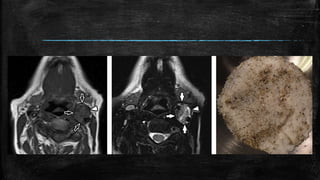

• #78 Salt and pepper” sign of paraganglioma. (a) Axial non-contrast enhanced T1-weighted image demonstrates a circumscribed mass (white arrowhead) splaying the internal and external carotid arteries and demonstrating a speckled appearance with foci of intrinsic bright T1 signal (white open arrows). (b) Axial T2-weighted imaging shows the mass (white arrowhead) to have areas of peripheral dark T2 signal (white solid arrows). (c) This pattern has been likened to the appearance of “salt and pepper” and is pathognomonic for paraganglioma.